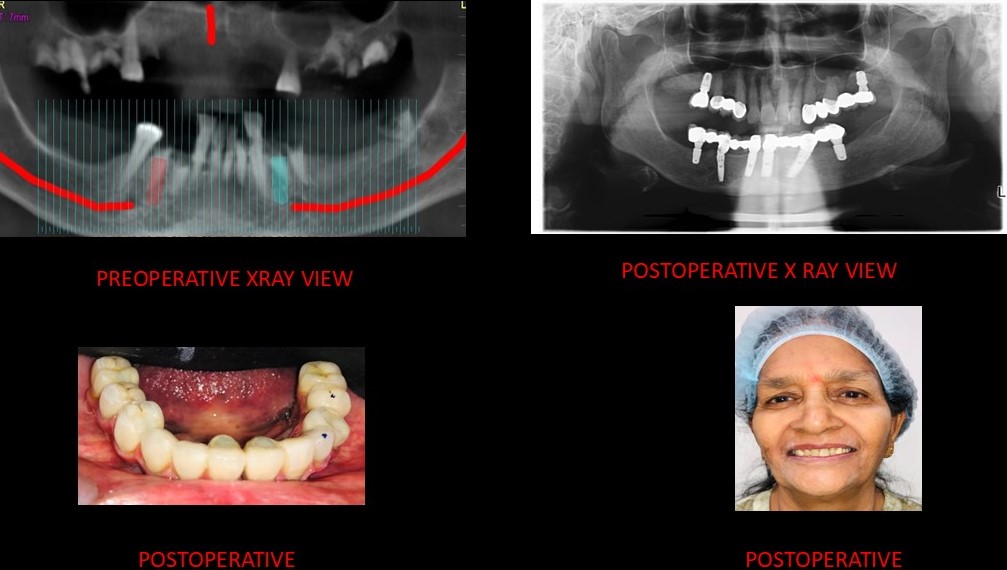

At Smile Dental Care Centre, we invite you to discover our exceptional dental care services in Delhi. We proudly hold the title of the best dental clinic in East of Kailash, Delhi and Faridabad, with a dedicated team of skilled dentists committed to preserving your oral health and enhancing your smile.

With two convenient locations in East of Kailash and Faridabad, we are even more accessible to serve your needs. Our state-of-the-art facility offers a wide range of services, including routine check-ups and advanced cosmetic and restorative procedures. Prioritizing your comfort, we employ the latest technology and gentle techniques for a pain-free experience.

At Smile Dental Care Centre, your health is our main concern. Our best dentist in Faridabad and Delhi provide friendly and personalized care to fit your needs and give you a happy, healthy smile. We’re also at the forefront of dental technology, using the latest advancements to ensure the best possible care for you. Get in touch today to set up your appointment!